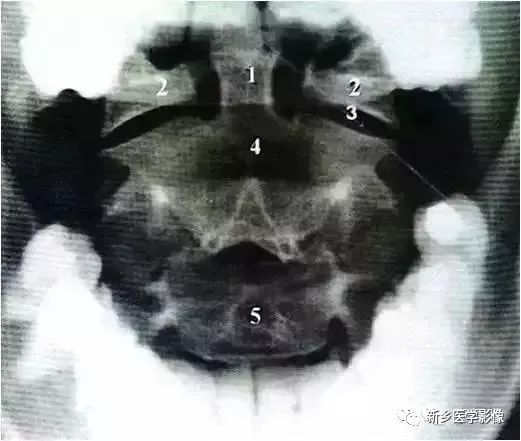

颈椎张口位

开口位片主要观察1.2颈椎有无骨折,先天缺如及环枢关节有无脱位及半脱位等情况,环枢关节半脱位一般会引起头晕,头痛,耳鸣,眼涨,等症状,临床上碰到有以上症状的,一般加拍颈椎开口位片。

十张口:指观察张口位投照的X线正位片。

(1)观察寰枢椎(2)看齿状突(3)观察寰椎椎弓(4)寰齿关节间隙

上位颈椎X光片,张口位

1 枢椎之齿突,2 寰枢之外侧块,3 寰枢关节,4 枢椎之椎体,5 第3颈椎